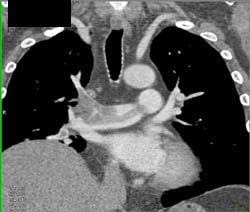

Pulmonary Embolism